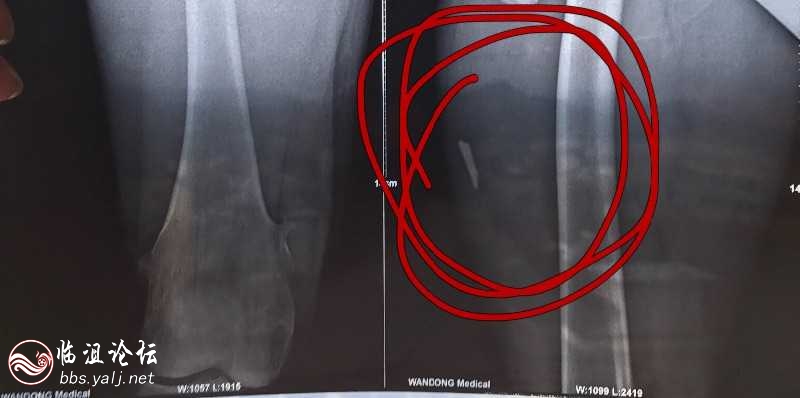

2012年11月11日下午15:30分本人因朋友间追逐而撞破玻璃门,割伤右侧大腿内侧长度9公分深度3公分,前往远安县人民医院外科二楼进行清创缝合由一位年轻医生进行伤口缝合,缝合13针。缝合后让我回家修养,未主动告知拍片检查。

2017年7月7日因近期右侧大腿疼痛难忍已无法正常行走,怀疑内部可能有残留玻璃碎片,为安全起见与7月7日上午8时前往远安县中医院阐述原因并要求拍片检查,大约10时30分拍片结果出来,诊断结果:大腿内侧现高密度结节影,怀疑为异物残留。

7日下午15时进行手术取出玻璃,玻璃长度3厘米,宽度0.7厘米。一端为尖锐型三角形,术后20分钟做头孢皮试呈现过敏,胸闷缺氧,胸部红痒起痘。吸了2个小时氧气才恢复。